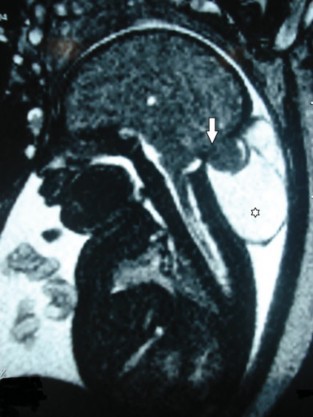

RM fetal. Corte sagital en ponderación T2. En la región occipital se aprecia un defecto óseo (flecha) que contiene tejido encefálico occipital, meninges y LCR, adoptando la apariencia de un voluminoso quiste (*). Se trata de un meningoencefalocele occipital.